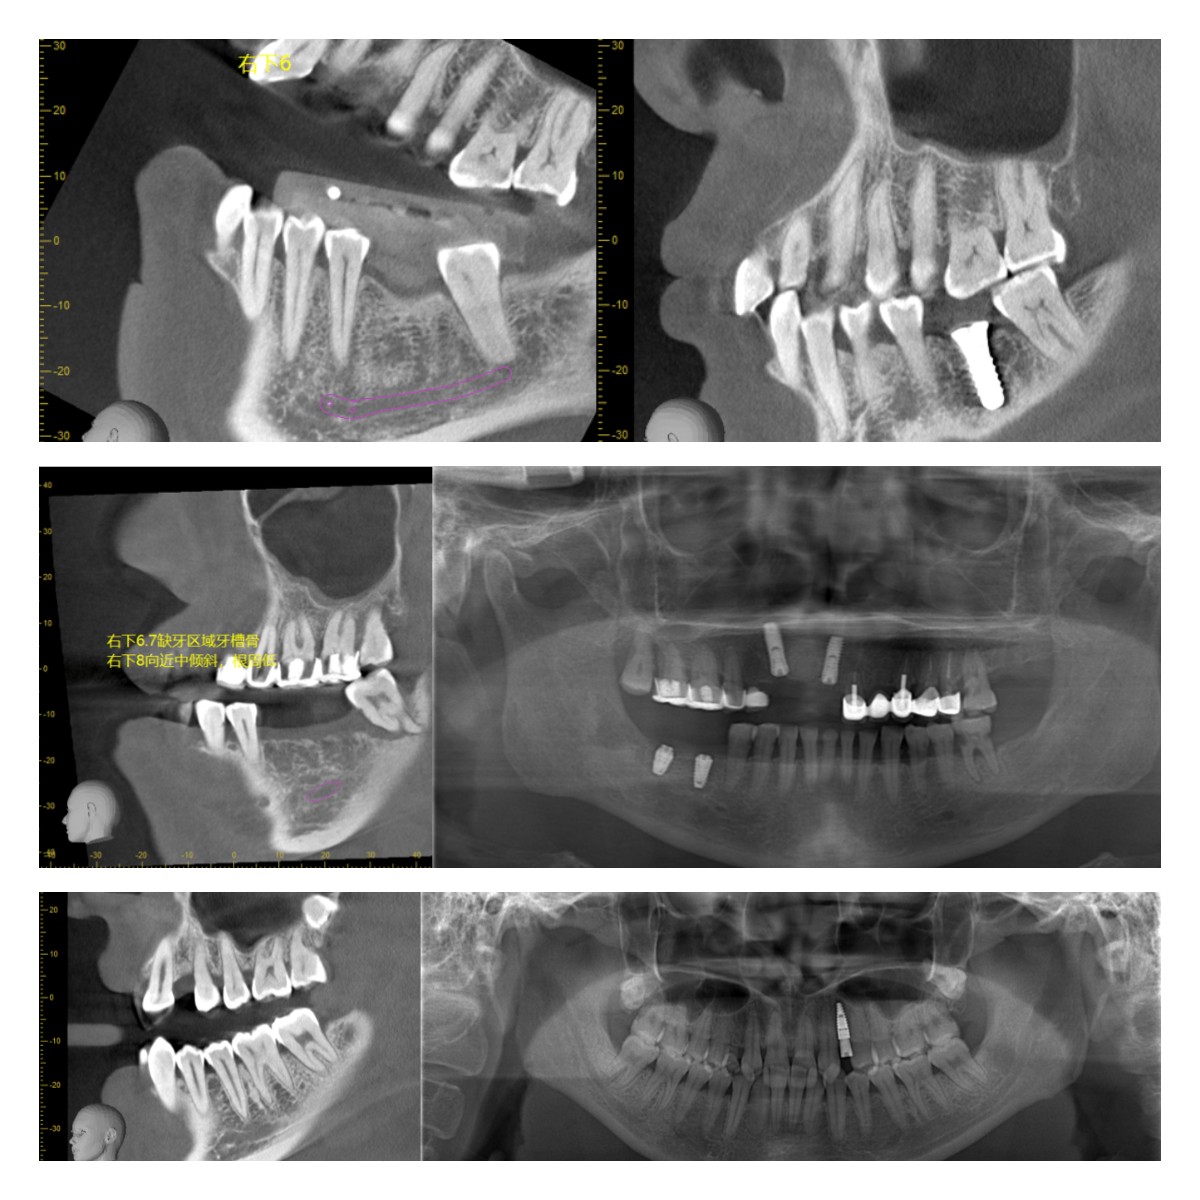

部分病例展示:

在這里,小編為大家一一解答~1、使用動(dòng)態(tài)導(dǎo)航進(jìn)行種植,即刻種植、即刻修復(fù),減少就診時(shí)間;2、傳統(tǒng)種植只能夠憑借經(jīng)驗(yàn)進(jìn)行種植,無(wú)法在手術(shù)過(guò)程中看見(jiàn)植入植體的位點(diǎn)、角度和深度,而動(dòng)態(tài)導(dǎo)航是可視化種植,按照設(shè)計(jì)好的種植方案,進(jìn)行手術(shù)并實(shí)時(shí)監(jiān)測(cè)手術(shù)過(guò)程,在術(shù)中遇到突發(fā)情況也可實(shí)時(shí)更改種植方案,降低手術(shù)風(fēng)險(xiǎn)。3、使用動(dòng)態(tài)導(dǎo)航進(jìn)行種植,無(wú)需開(kāi)刀,避免縫合拆線的二次創(chuàng)傷,微創(chuàng)手術(shù),出血少,愈合快。4、傳統(tǒng)的導(dǎo)板種植,在后牙區(qū)域受限,無(wú)法使用,且散熱慢,容易引起并發(fā)癥,導(dǎo)航進(jìn)行全口種植,對(duì)于任何缺牙區(qū)都可以使用導(dǎo)航種植,減少并發(fā)癥。5、傳統(tǒng)手術(shù)方式無(wú)法解決的穿顴穿翼手術(shù)、無(wú)牙頜手術(shù)、失敗再修復(fù)等復(fù)雜病例,動(dòng)態(tài)導(dǎo)航都可以適用,具備顯著的優(yōu)勢(shì)。